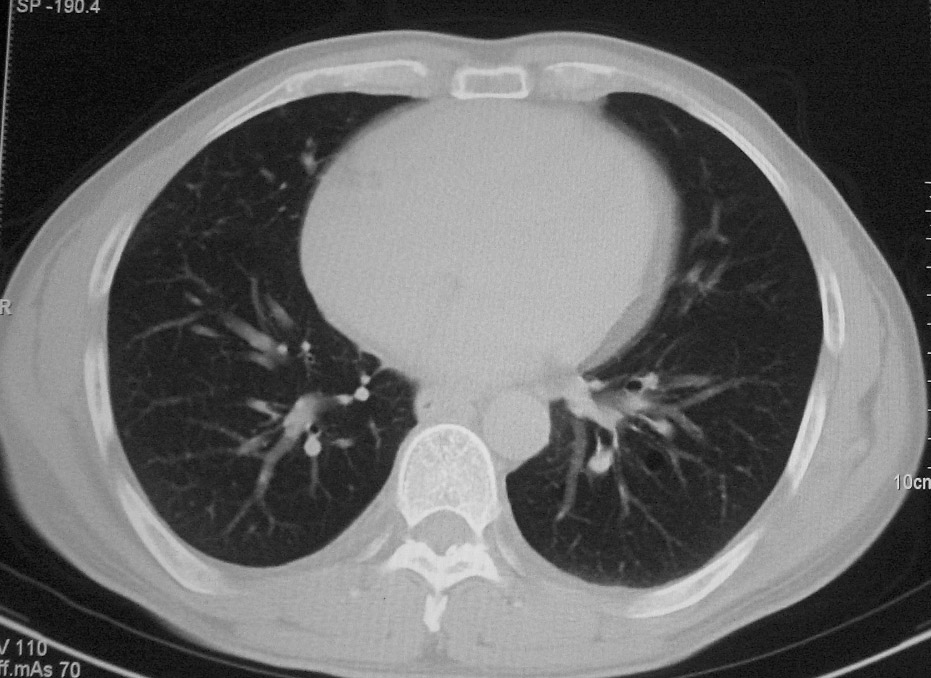

标题: CT5485:[原创]肺部占位请讨论

右上叶支气管肺癌并右上叶阻塞性不张,右侧少量胸腔积液.

右上肺中央性肺癌伴右侧胸腔少量积液!右上肺胸膜下还有一小病灶,不完全排除结核,但个人支持恶性肿瘤!建议早穿刺活检。

右肺上叶中央型肺癌并上叶肺不张、纵隔淋巴结肿大.右侧少量胸腔积液。

右上肺中心型肺癌并肺不张,纵膈淋巴结肿大。右侧少量胸腔积液。

右肺上叶支气管后壁增厚,呈鼠尾状狭窄,纵隔内未见明显增大的淋巴结影,考虑为中央型肺癌伴右上肺不张

右肺上叶不张,考虑中央型肺癌。右侧胸膜肥厚

右肺上叶中央型肺癌并阻塞性炎症、阻塞性肺不张……

右上肺癌,肺不张,纵隔淋巴结肿大